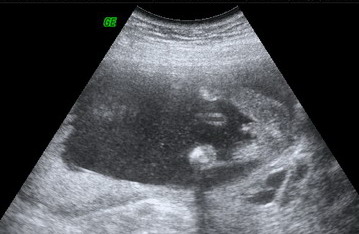

mármint a méhlepény?[quote] írta:hogy a méhem rálóg a méhszájra

[quote]A írta:kkor most aztán nincs ám virgonckodás, amíg el nem mászik onnan!